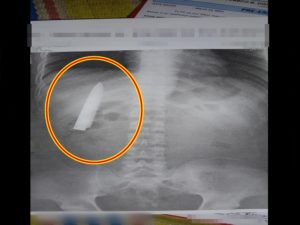

Passenger Armed With Knife at Iloilo Airport Shot A 54-year-old passenger was shot in the chest at Iloilo International Airport in Cabatuan, Iloilo, on Wednesday afternoon after being found carrying a knife. The incident occurred around 4:44 p.m. in the pre-departure security screening area. According to the Office for Transportation Security (OTS), a security officer … Read more